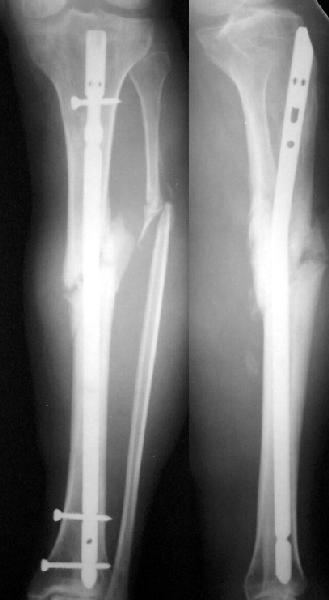

No hollow reamers and nails are still availble yet, so UTN 10 mm was used. After perQ osteotomy of the fibula i tried to open the canal, and the awl was passed to the distal fragment only after closed mobilization of the site to make some antecurvation. It resulted with some anterior translation of the distal fragment :( After impaction the nail was locked dynamically. Images attached. Comments/critics are

welcome.

get_image.jpg

16KB (17241 bytes)

I believe this nailed nonunion of the tibia shaft will likely go on to uneventful healing. Good job.

I'm not clear if you opened the fracture site and used an awl or if you used an awl through the nail entry site. The latter is preferred although often difficult and sometimes impossible.

Today the case was criticized at the week clinical report for the antecurvation deformity... Unhappily our vice-director tries to prove that such a malalignment is of great clinical importance.

TAD> I'm not clear if you opened the fracture site and used an awl or

TAD> if you used an awl through the nail entry site. The latter is

Yes, nailing was closed, the canal was opened through the nail entry site.

I would expect the deformity of the case of nailed tibia shaft nonunion (slight apex posterior and slight posterior translation) to be of no definite and small theoretical clinical importance.